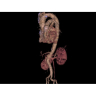

Позволяет проводить комплексные исследования всех анатомических зон, включая нейровизуализацию, ангиографию, исследования органов грудной и брюшной полости. Особенно эффективен для раннего выявления онкологических заболеваний.

Обеспечивает высокую точность при кардиологических исследованиях, визуализации костных структур и суставов. Подходит для динамического наблюдения в ходе лечения.